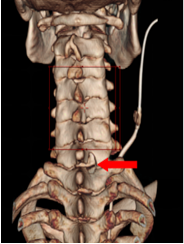

为了把创伤降到最低,同时探查清楚病变性质,脊柱外科李志敏医疗团队在沈翀主任医师、肖荣驰主任医师的指导下,决定采用脊柱内镜下 Key-hole(钥匙孔)技术。

这项技术是在患者颈部后方打开一个「钥匙孔」大小的通道,在尽可能少破坏正常骨骼结构的情况下,通过内镜高清探头精准抵达病灶位置。

硬币大小切口与钥匙孔骨窗